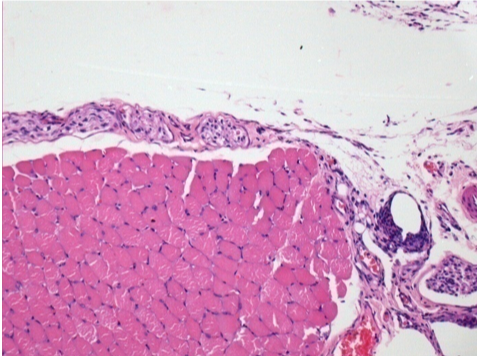

0,5 мл (5x 0,1 мл) підшкірна ін'єкція Ендопіл в праву підшкірну претибіальну ділянку.

Л:200x-Контроль-ПШ

П-10днів-ПШ-200X